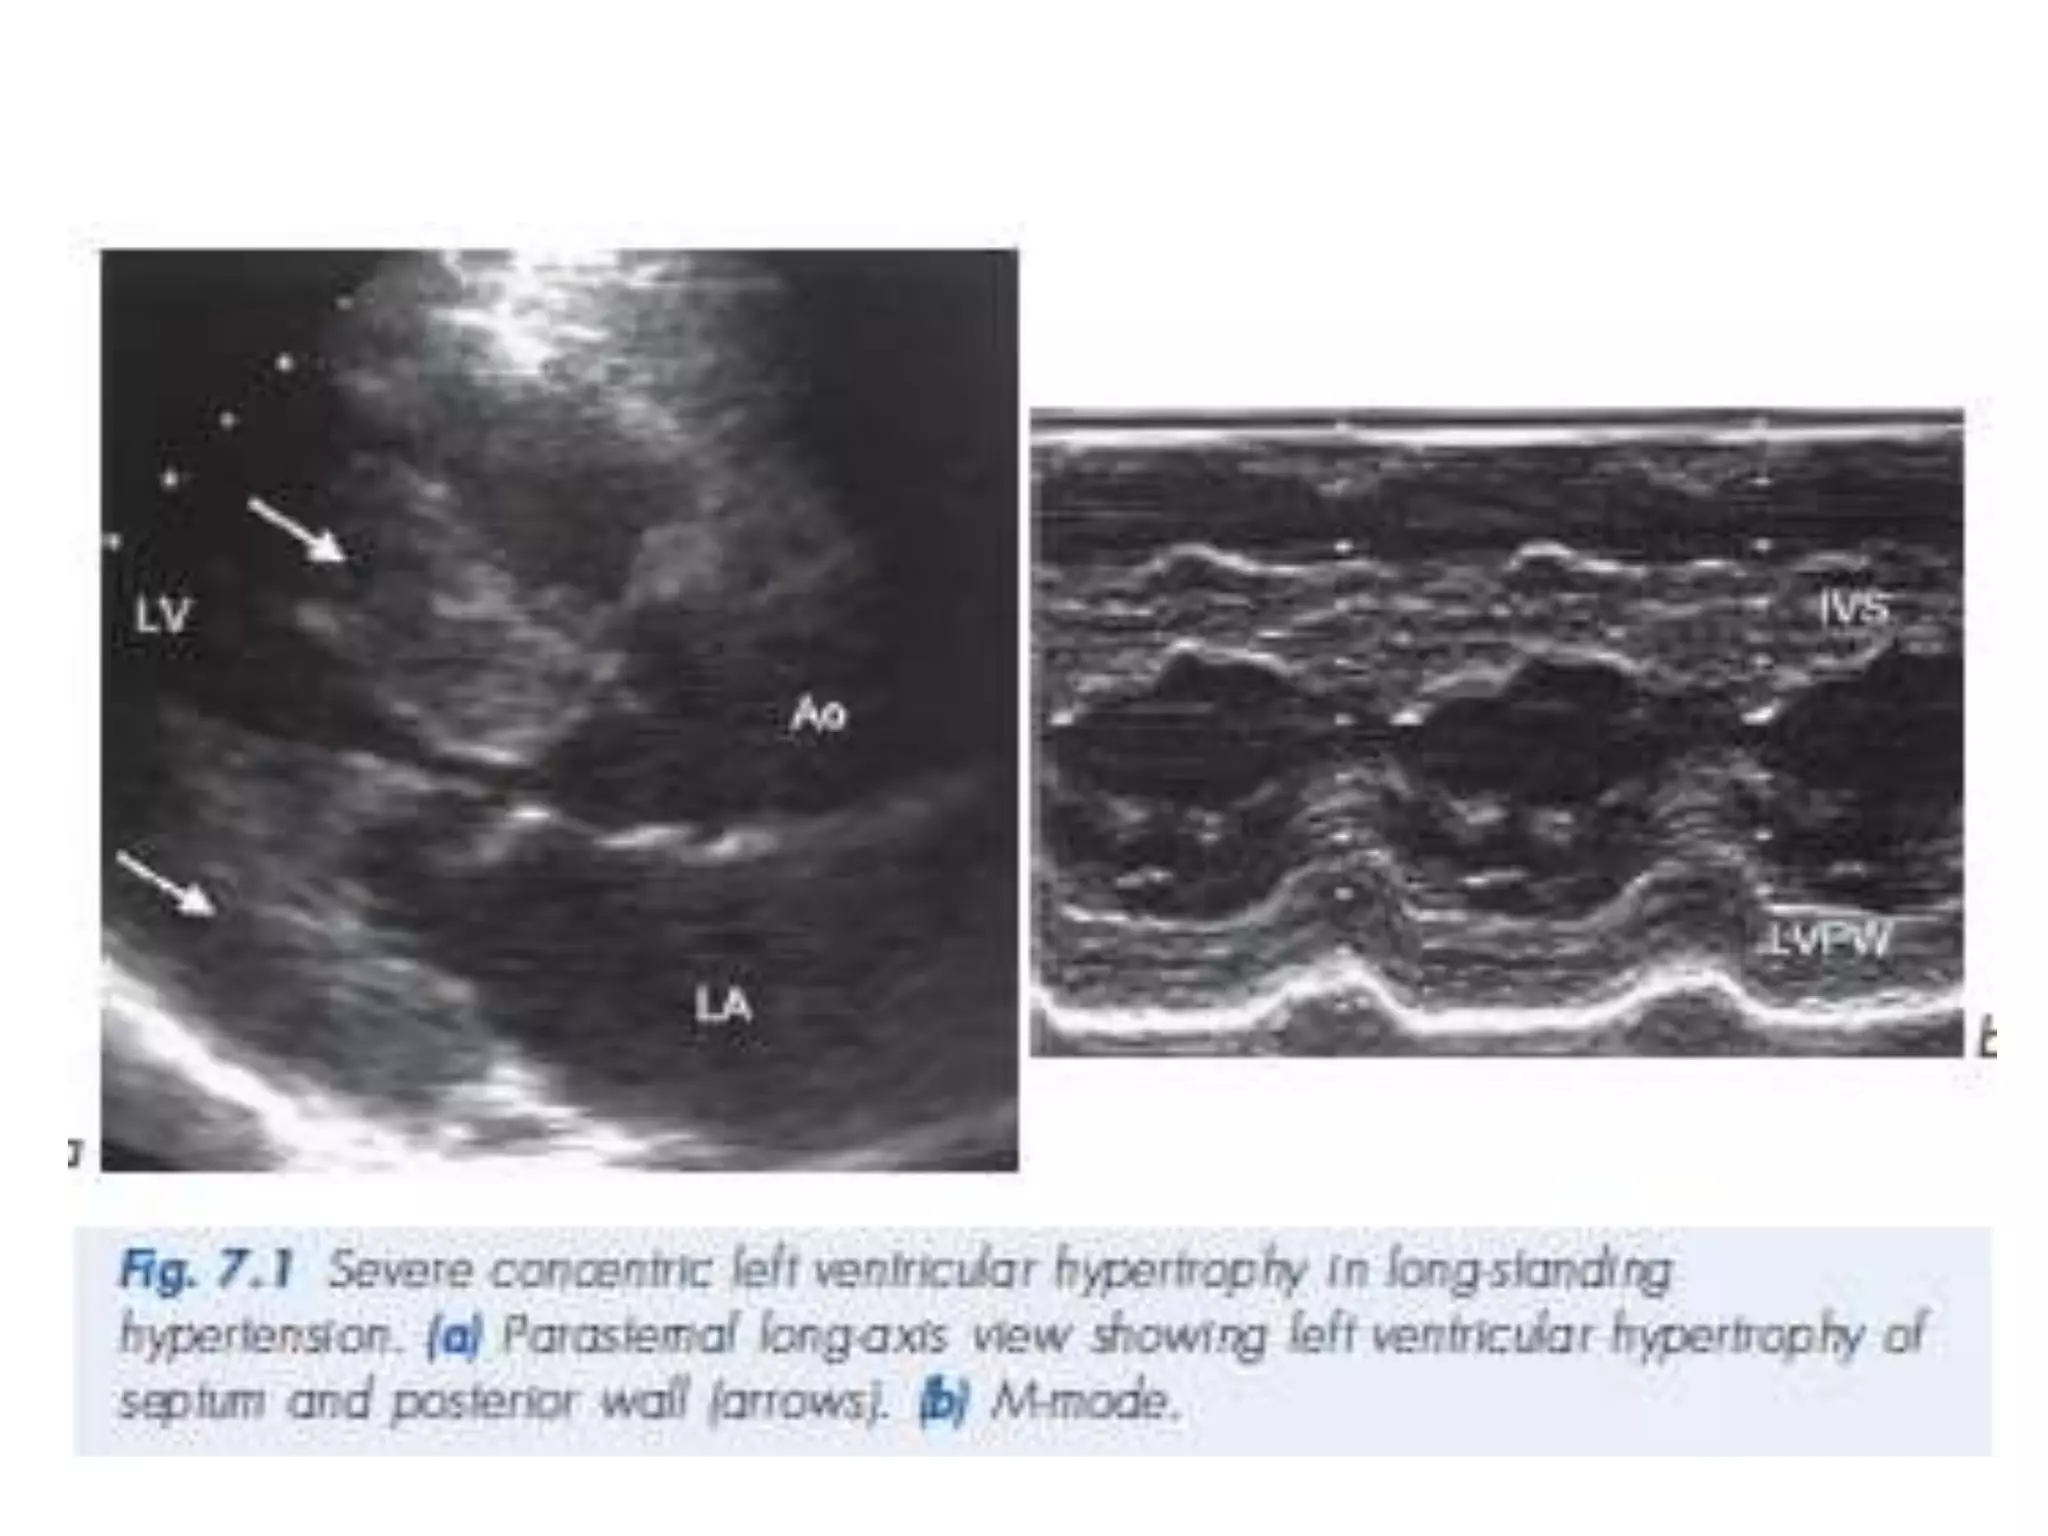

HCM